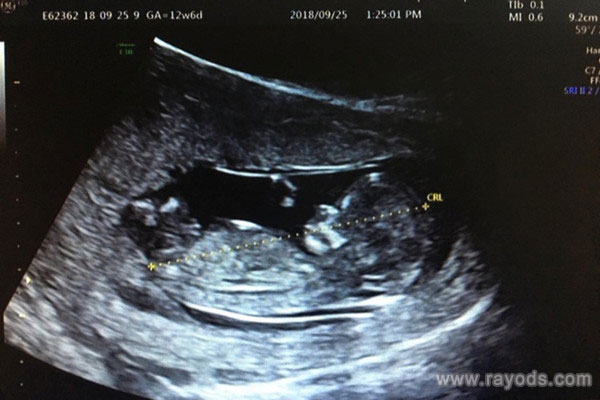

据说nub点凸出的是男孩的生殖器官,而女孩这里是不大明显外凸的,因此nub点这里一般都是平行的。因此网上就总结出了一些个说法,如果nub上翘或者凸出的生男孩的几率大,反之nub点平行的生女孩的几率大。虽然nub平行女孩居多,但生活中也有平行生了男孩的情况,大家可以看看已生宝妈分享的个人经历。

@网友:nub点就是尾椎骨上的突起点,突起的延长线与后背脊椎的延长线之间的角度,如果为平行甚至为负角度则为女孩,角度超过30则为男孩。我的就是大于30度,感觉上翘的不是平行的,已生男孩。

@网友:11-13周做nt的时候,所有的胎儿都会在双腿之间长出一个小肉球,而这个肉球的角度则会显示出它是个男孩还是女孩。看过nub示意图见下面的图片,11周准确率为50%,12周13周会增加到80-90%,到了14周几乎可以达到100%还是女孩。